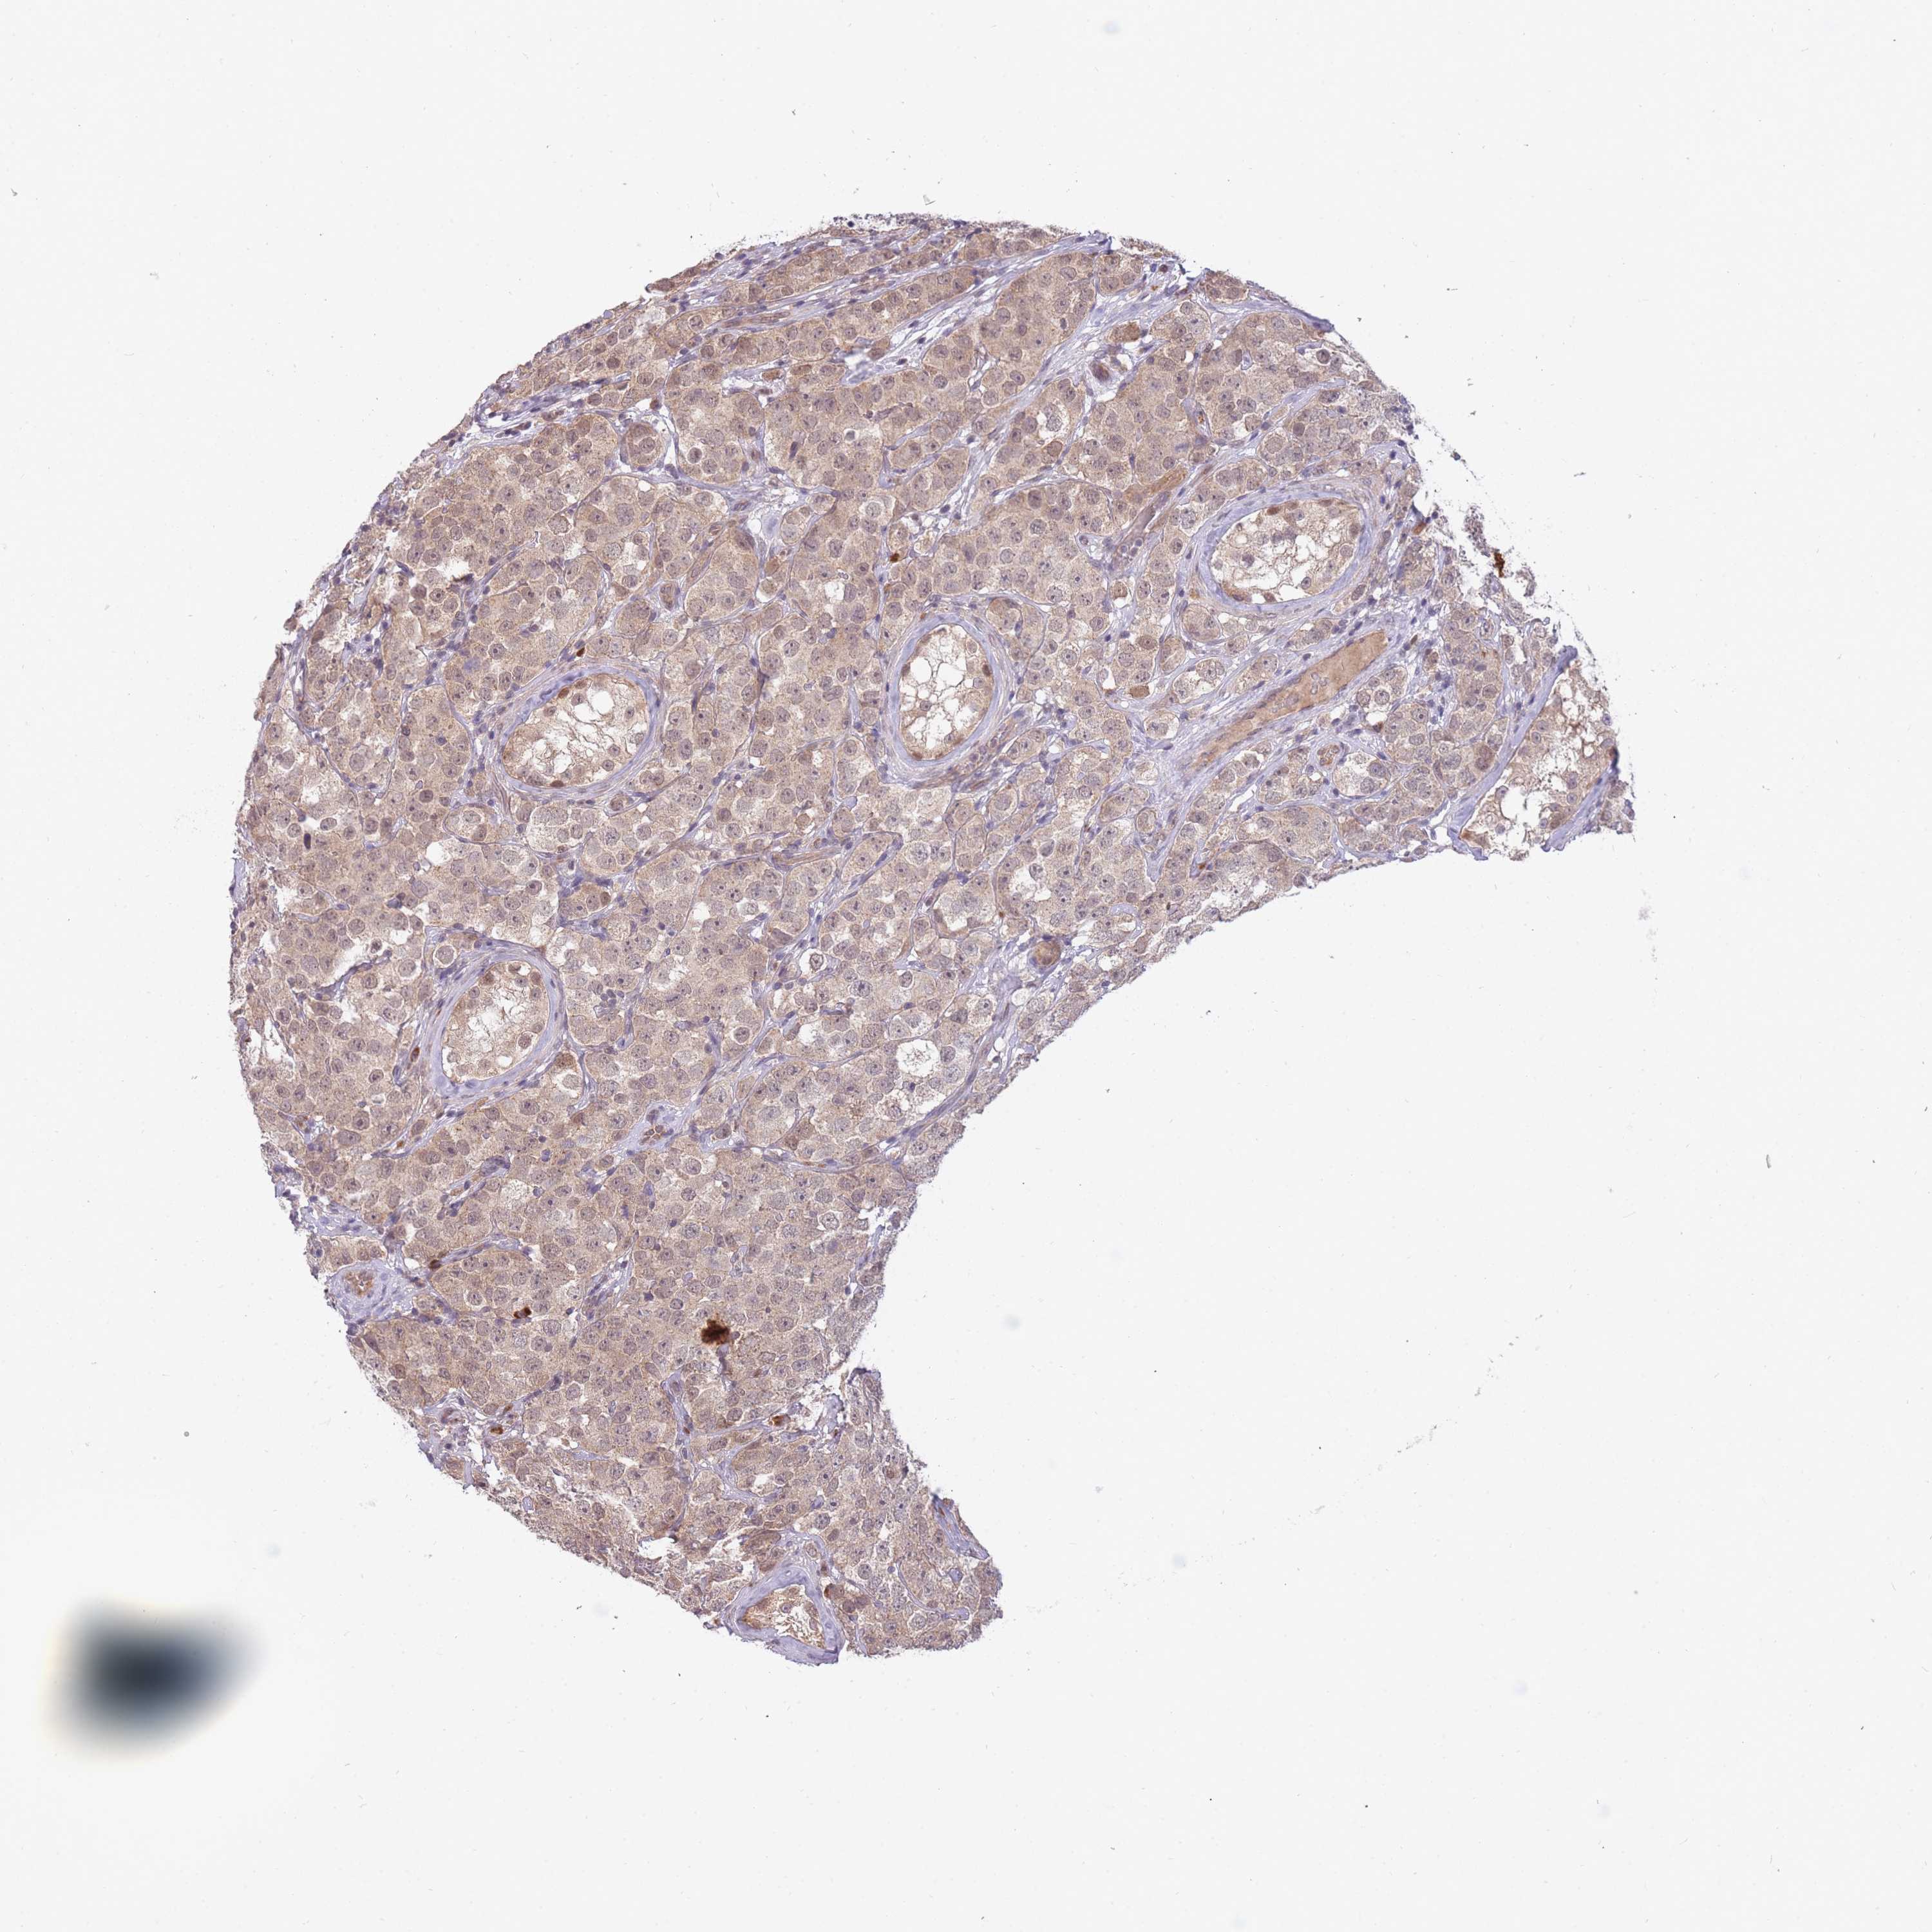

TESTIS CANCER - Protein expressioni

A mouse-over function shows sample information and annotation data. Click on an image to view it in a full screen mode. Samples can be filtered based on level of antibody staining by selecting one or several of the following categories: high, medium, low and not detected. The assay and annotation is described here.

Note that samples used for immunohistochemistry by the Human Protein Atlas do not correspond to samples in the TCGA dataset.

Antibody stainingi

Antibody staining in the annotated cell types in the current human tissue is reported as not detected, low, medium, or high, based on conventional immunohistochemistry profiling in selected tissues. This score is based on the combination of the staining intensity and fraction of stained cells.

Each image is clickable and will lead to virtual microscopy that enables deeper exploration of all samples and also displays staining intensity scores, fraction scores and subcellular localization as well as patient and tissue information for each sample.

Antibody HPA042733

Antibody CAB037186

Staining

High

Medium

Low

Not detected

Intensity

Strong

Moderate

Weak

Negative

Quantity

>75%

75%-25%

<25%

None

Location

Nuclear

Cytoplasmic/membranous

Cytoplasmic/membranous,nuclear

Carcinoma, Embryonal, NOS

Seminoma, NOS